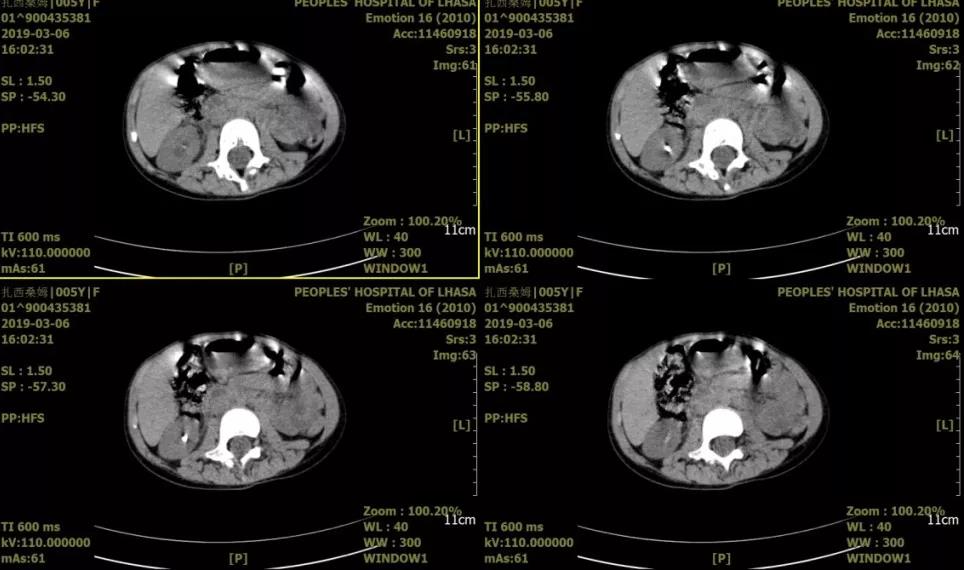

患儿,女,5岁,主因“右侧腰部疼痛1天”就诊,术前诊断:1.右输尿管结石,2.右肾结石。入院后决定一期行输尿管支架植入术,二期行mPCNL